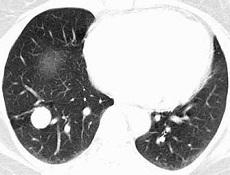

炎性假瘤為一種特發(fā)的非特異性慢性增殖性炎癥,臨床表現(xiàn)類似腫瘤,但實質(zhì)上是炎癥,故名炎性假瘤。本病較為常見,病因尚不清楚,目前多認為是一種免疫反應性疾病。本病可發(fā)生于任何年齡,40歲以上較為多見,男性多于女性,可單眼或雙眼發(fā)病,小部分患者可伴有身體其他部位同類病變。眼眶炎性假瘤可波及眼內(nèi)各種軟組織,但可主要發(fā)生于某種結(jié)構(gòu),如眼蜂窩組織、眼外肌或淚腺。根據(jù)組織學改變,本病可分為淋巴細胞浸潤型、纖維增生型和混合型。臨床表現(xiàn)主要有眼痛、眼瞼和結(jié)膜紅腫、眼球突出、眼球運動障礙及視力下降等。用皮質(zhì)類固醇等抗炎治療可使病情緩解,但易復發(fā)。